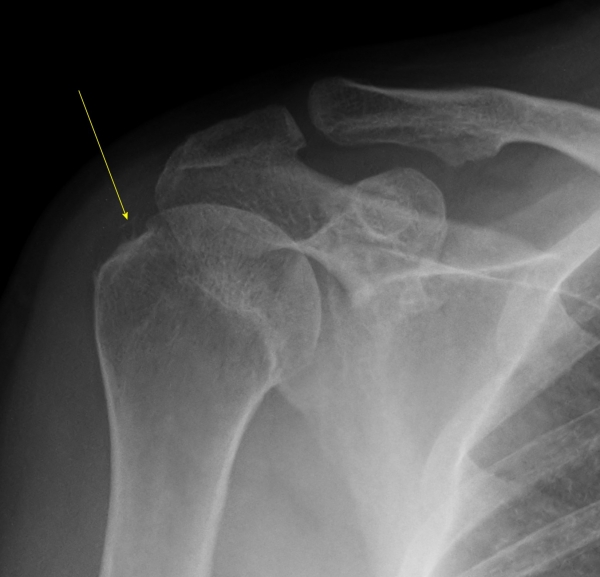

¹æ»ç¼± °Ë»ç :  1Â÷ ¹æ»ç¼± °Ë»ç¿¡¼­ ±Ø»ó°Ç³» °íÀ½¿µ ¼®È¸°¡ °üÂûµÊ(»çÁø 5).

ÃÊÀ½ÆÄ ¼Ò°ß :  ±Ø»ó°Ç Á¾´Ü¸é°Ë»ç¿¡¼­ ÈĹæÀ½¿µÀ» º¸ÀÌ´Â °í¿¡ÄÚ ¼®È¸È­ µ¢¾î¸®°¡ °üÂûµÈ´Ù(»çÁø 1).